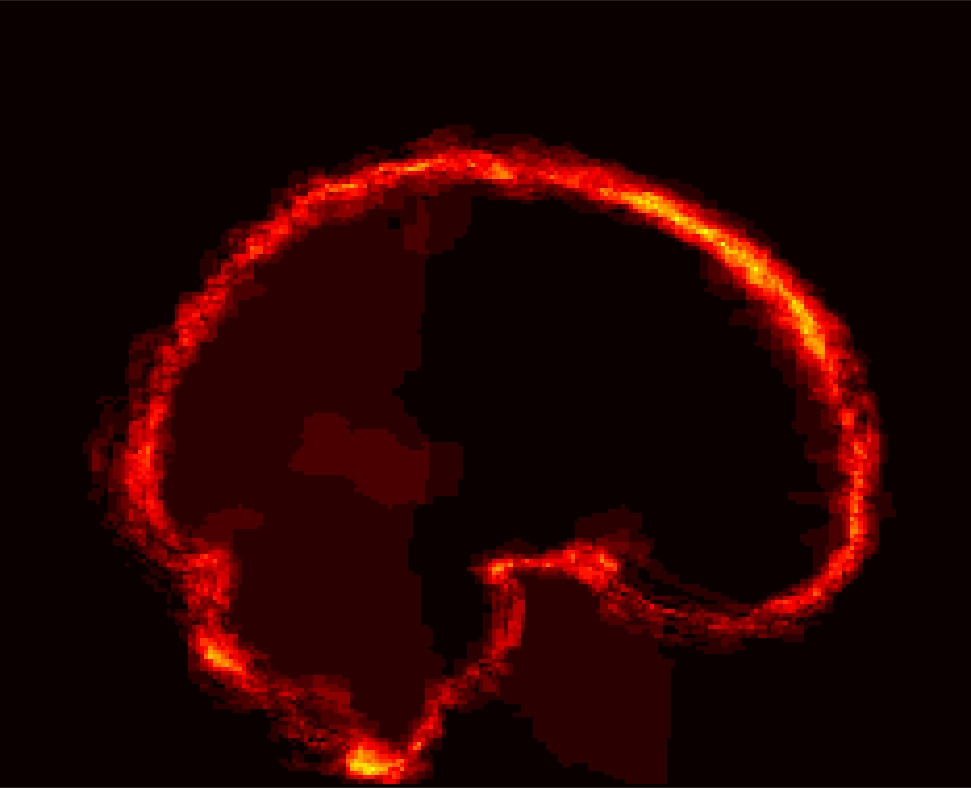

Fig. 9 (left) visualizes the average brain mask errors for IBSR and LPBA40. All images are first affinely registered to the atlas. Then we transform the gold-standard expert segmentations as well as the automatically obtained brain masks of the different methods to atlas space. We compare the segmentations by counting the average over- and under-segmentation errors over all cases at each voxel. This results in a visualization for areas of likely mis-segmentation. Our PCA model, ROBEX, BEaST (BEaST*) and BET perform well on these two datasets. Compareed to our model, ROBEX, BEaST (BEaST*) and BET show larger localized errors, e.g., at the boundary of the parietal lobe, the occipital lobe and the cerebellum. While MASS, BSE and CNN perform well on the LPBA40 dataset, they perform poorly on the IBSR dataset. This is in particular the case for the CNN approach.

Finally, Fig. 9 (right) shows the average segmentation errors on the BRATS and TBI datasets: our PCA method shows fewer errors than most other methods in these two abnormal datasets. MASS also shows few errors, while ROBEX, BEaST (BEaST*) and BET exhibit slightly larger errors at the boundary of the brain. CNN and BSE particularly show large errors for the BRATS dataset presumably again due to the coarse resolution of the BRATS data.

IBSR BRATS [Uncaptioned image]

PCA [Uncaptioned image] [Uncaptioned image] [Uncaptioned image] [Uncaptioned image] [Uncaptioned image] [Uncaptioned image]

ROBEX [Uncaptioned image] [Uncaptioned image] [Uncaptioned image] [Uncaptioned image] [Uncaptioned image] [Uncaptioned image]

BEaST* [Uncaptioned image] [Uncaptioned image] [Uncaptioned image] [Uncaptioned image] [Uncaptioned image] [Uncaptioned image]

MASS [Uncaptioned image] [Uncaptioned image] [Uncaptioned image] [Uncaptioned image] [Uncaptioned image] [Uncaptioned image]

BET [Uncaptioned image] [Uncaptioned image] [Uncaptioned image] [Uncaptioned image] [Uncaptioned image] [Uncaptioned image]

BSE [Uncaptioned image] [Uncaptioned image] [Uncaptioned image] [Uncaptioned image] [Uncaptioned image] [Uncaptioned image]

CNN [Uncaptioned image] [Uncaptioned image] [Uncaptioned image] [Uncaptioned image] [Uncaptioned image] [Uncaptioned image]

LPBA40 TBI

BEaST [Uncaptioned image] [Uncaptioned image] [Uncaptioned image] [Uncaptioned image] [Uncaptioned image] [Uncaptioned image]

Figure 9: Examples of 3D volumes of average errors for the normal IBSR and LPBA40 datasets, as well as for the pathological BRATS and TBI datasets. For IBSR/BRATS, we show results for BEaST*. Images and their brain masks are first affinely aligned to the atlas. At each location we then calculate the proportion of segmentation errors among all the segmented cases of a dataset (both over- and under-segmentation errors). Lower values are better (a value of 0 indicates perfect results over all images) and higher values indicate poorer performance (a value of 1 indicates failure on all cases). Clearly, BSE and CNN struggle with the BRATS dataset whereas our PCA method shows good performance across all datasets.